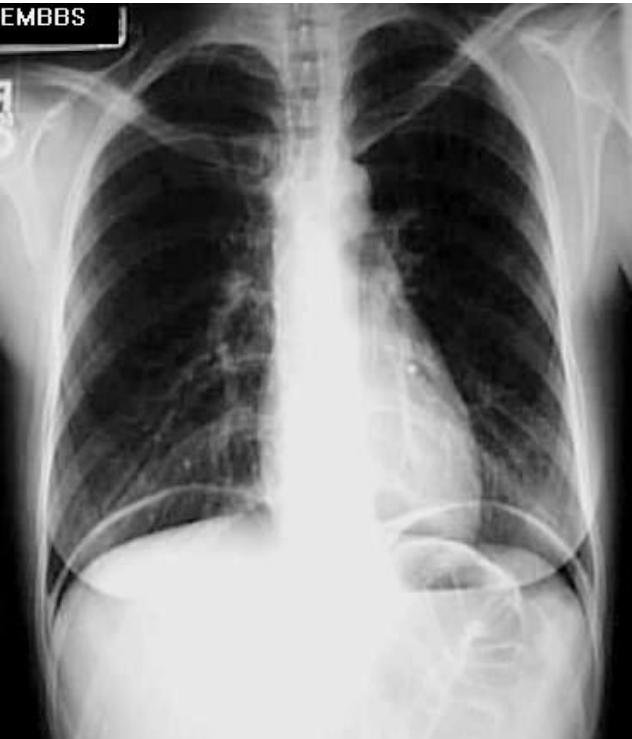

Ao exame: fácies de dor, temperatura axilar de 38.5 °C, hipocorada +/4+, pressão arterial 100/60 mmHg, pulso 110 bpm, frequência respiratória 32 RPM. Desidratada ++/4. Abdome distendido, difusamente doloroso, com presença de sinal do rebote. Hipertimpanismo difuso. Ruídos hidroaéreos abolidos. Sem outros achados. O cirurgião assistente solicitou rotina radiológica para abdome agudo, cuja grafia de tórax em PA ortostático é apresentada abaixo.

Na ocasião da reinternação, a paciente foi admitida em franco quadro de abdome agudo. Chama a atenção em sua história o início súbito de dor, bem caracterizada em termos cronológicos (achado comum na perfuração ulcerosa). Clinicamente ainda, os achados de febre, taquicardia, desidratação e íleo corroboram esse diagnóstico. A presença do sinal do rebote caracteriza estar havendo irritação peritoneal, plenamente justificada pela peritonite química, comum a esse tipo de complicação da doença ulcerosa. Por fim, o achado radiológico de pneumoperitôneo documenta a presença de perfuração de víscera oca. Nota-se ainda ao raio-X simples a presença de alça em sentinela ao nível do epigástrio, bastante comum em casos como esse.